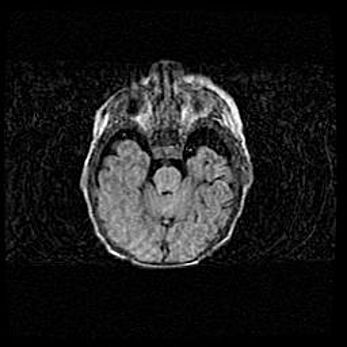

Церебральная ишемия II.

Возраст: 7 дней

Вес: 3350 г

Пол: женский

Окружность головы: 35 см

Срок гестации: 39 недель

Ишемия головного мозга – это состояние, которое развивается в ответ на кислородное голодание вследствие недостаточного мозгового кровообращения. У новорожденных она является следствием дефицита кислорода, что ведет к метаболическим расстройствам различной степени тяжести в тканях головного мозга, в том числе к развитию коагуляционных некрозов и гибели нейронов.